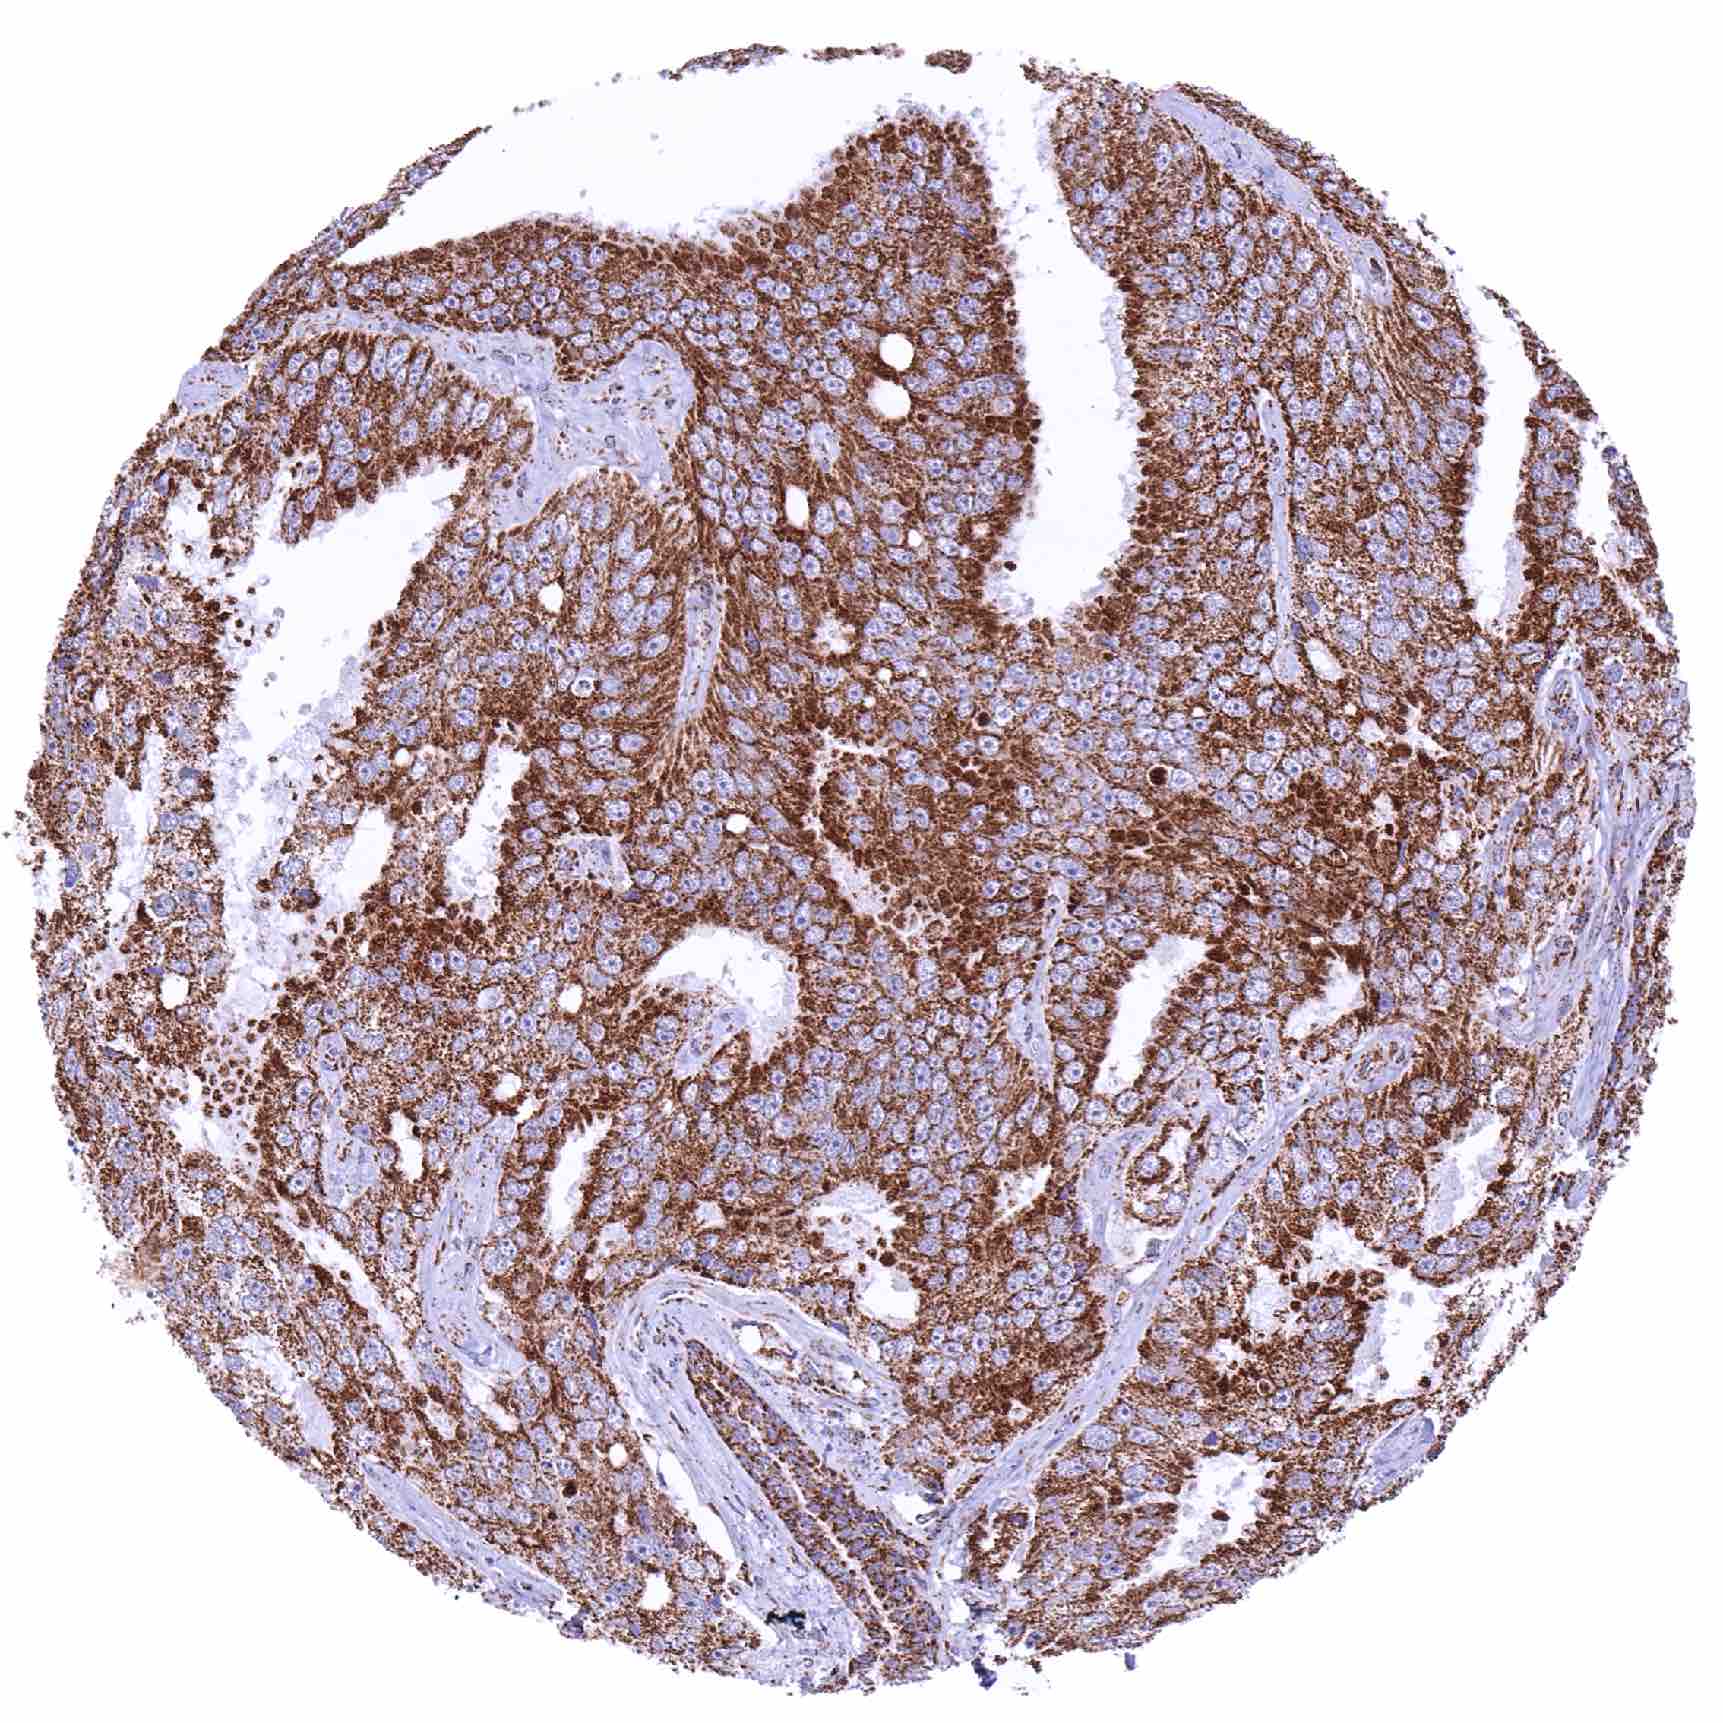

Pancreas – Ductal adenocarcinoma showing a strong SDHA staining of tumor and stromal cells